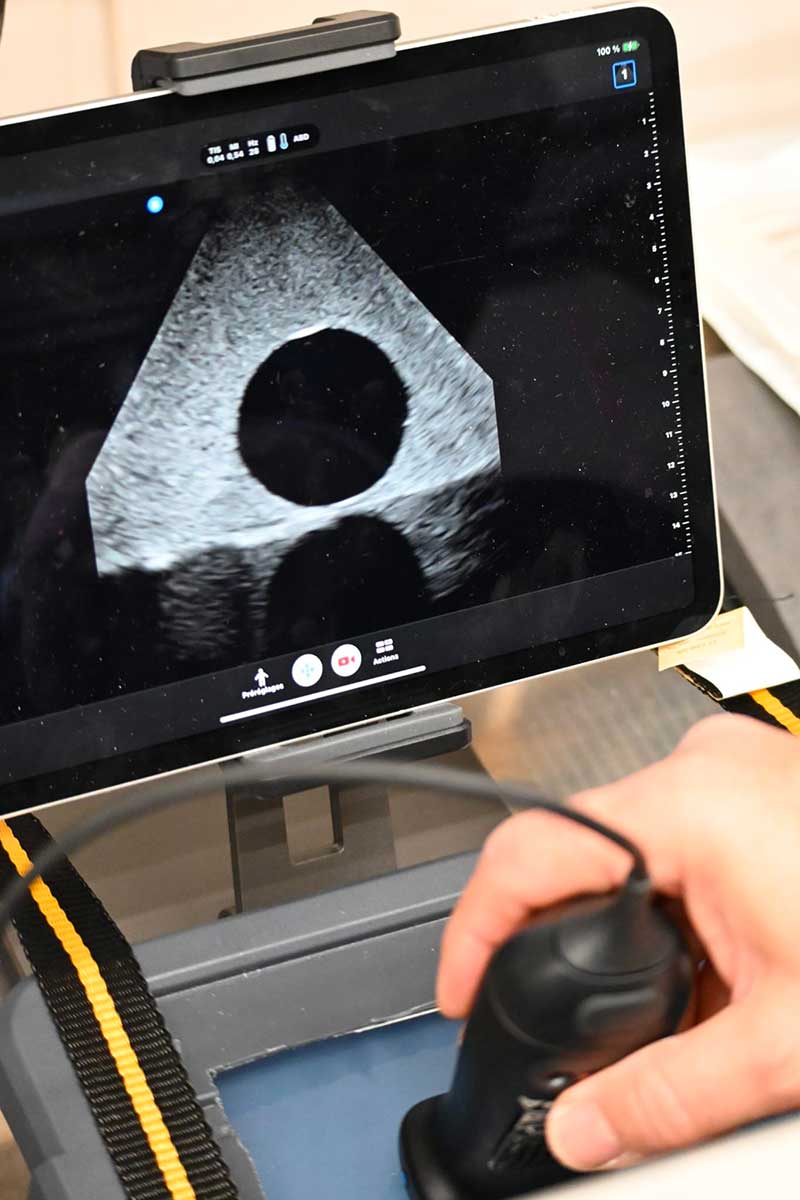

Parmi le groupe de 12 chercheurs se trouvaient le Pr Vincent Vidal, le Dr Jérôme Soussan (Hôpital Nord) et le Dr Guillaume Louis (Hôpital de la Timone). Malgré ces conditions extrêmes, ils sont parvenus à démontrer la faisabilité de procédures de radiologie interventionnelle sous guidage échographique pour traiter un cas de colique néphrétique surinfectée (ponction directe et technique de Seldinger par cathétérisme).

Pour affiner et tester les procédures d’intervention, l’équipe a travaillé sur des simulateurs : des blocs de gel d’agar-agar contenant des cibles qui représentaient les abcès à drainer. La conception de ces modèles et de la procédure d’intervention en caisson a nécessité plus de 6 mois de travail, en partenariat avec le Laboratoire d’Imagerie Interventionnelle Expérimentale (LIIE), dirigé par le Dr Pauline Brige, et Novespace qui contrôlait tous les paramètres.